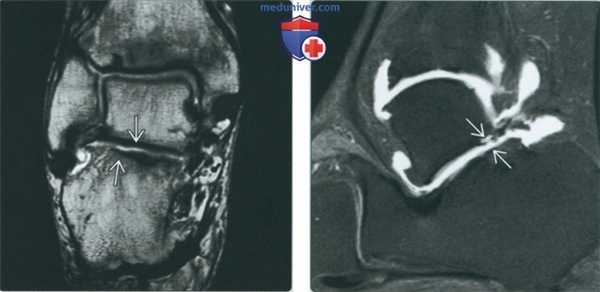

(Слева) МР-артрография в режиме Т1ВИ, коронарный срез, пациент 25 лет: визуализируется обширное повреждение суставного хряща подтаранного сустава вследствие перелома пяточной кости.

(Справа) МР-артрография в режиме Т1 ВИ, сагиттальный срез: спереди видны участки неизмененного хряща, а сзади - выраженное его истончение. В голеностопном суставе отмечаются признаки остеоартроза. У этого пациента подтаранный сустав сообщается с полостью голеностопного сустава. Лечение заключалось в артродезе обоих суставов.